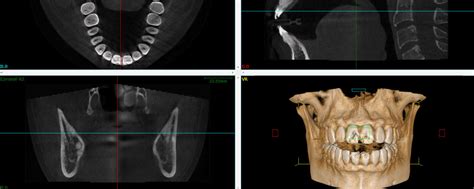

Tecnología Avanzada para Diagnósticos Precisos

La clínica está equipada con tecnología de última generación para ofrecer diagnósticos precisos y tratamientos eficaces. Un ejemplo de ello es el SCANNER Cone Beam Planmeca Promax, que permite obtener imágenes tridimensionales de alta resolución con mínima radiación.

Este escáner ofrece diversos estudios, incluyendo:

- Crestas oseas para estudio reglado para implantes.

- Localización de conductos radiculares y dx. periapical.

- Diagnóstico de la vía aerea, y Oído.

Esta tecnología es fundamental para la planificación de implantes dentales, la localización de conductos radiculares y el diagnóstico de diversas patologías.